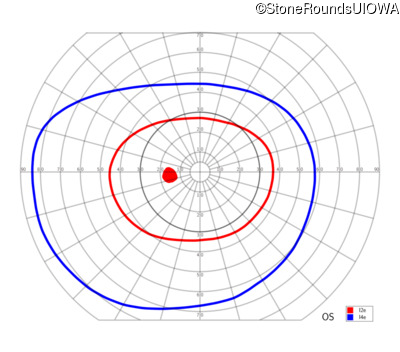

| Age at visit: 6 years |

| Age at visit: 11 years |

| Age at visit: 14 years |

| OD | OS | ||

| Age at visit: 14 years (Visit 2) |

| OD | OS | ||